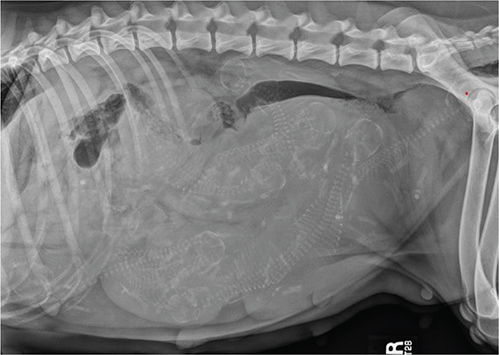

Physical examination findings were underweight (body condition score of 3/9 [Royal Canin© scale])4 and a moderate amount of nonfetid dark brown vulvar discharge. A large number of fetuses (fetal heart rates ranged between 200 and 250/beats per minute [bpm]) were observed via focal transabdominal ultrasonography. Serum progesterone concentration was 1.25 ng/ml. Bloodwork findings included mild normocytic normochromic anemia (categorized regenerative due to anisocytosis and polychromasia), mild monocytosis, mild hypocalcemia, and mild hyponatremia. Additional tests included leptospirosis witness test (WITNESS® Lepto, Zoetis, Parsippany, NJ), Brucella canis rapid slide agglutination test (D-TEC® CB, Zoetis), canine herpesvirus titer (Colorado State University, Fort Collins, CO), and SNAP 4Dx testing (anaplasma, ehrlichia, Lyme, and heartworm) (SNAP® 4Dx Plus Test, Idexx, Westbrook, ME); all were negative. Ten premature fetuses were counted (abdominal radiography), and their immaturity was determined based on the level of calcification, without evidence of fetal death (Figure 1). An immediate cesarean surgery with ovariohysterectomy was recommended but was declined by the owner. As the patient appeared stable, outpatient therapy was discussed initially; however, another fetus aborted necessitating overnight hospitalization. Therapies included intravenous lactated Ringer’s solution (90 ml/kg/day [Excel®, B. Braun Medical Inc., Bethlehem, PA]), subcutaneous terbutaline (0.03 mg/kg three times a day [Brethine®, Hikma Pharmaceuticals PLC, London, United Kingdom]), oral altrenogest (0.088 mg/kg once a day [Regu-Mate®, Merck Animal Health, Rahway, NJ]), oral amoxicillin and clavulanate potassium (14 mg/kg twice a day [Clavamox®, Zoetis, Parsippany, NJ]), oral clindamycin (11.8 mg/kg twice a day [Cleocin®, Lannett Company, Inc., Philadelphia, PA]), and oral fenbendazole (50 mg/kg once a day for 3 days [Panacur®, Merck Animal Health, Rahway, NJ]). Both aborted fetuses were submitted for necropsy, and were premature (lack of hair growth).

Fig. 1.

Figure 1. Right lateral abdominal radiograph (50 days after breeding), note the 10 fetuses and poor calcification (immaturity).